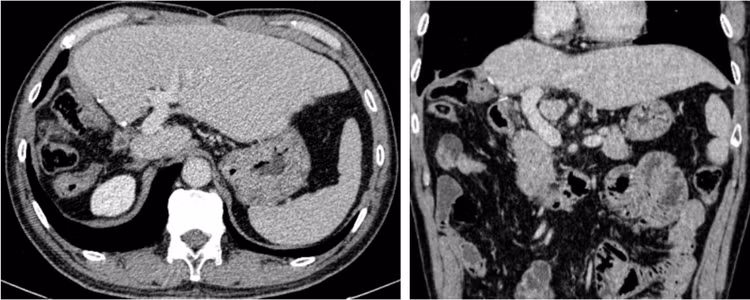

Cách đây 4 năm, bệnh nhân N.T.Đ (64 tuổi) được chẩn đoán ung thư biểu mô tế bào gan (HCC) lớn gan phải giai đoạn muộn, có huyết khối tĩnh mạch cửa lan thân chung và lan sang tĩnh mạch cửa bên trái trên nền viêm gan B, xơ gan.

Hình ảnh phim chụp cắt lớp vi tính u lớn gan phải kèm huyết khối tĩnh mạch cửa lan vào thân chung và tĩnh mạch cửa trái của người bệnh N.T.Đ - Ảnh BVCC